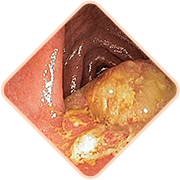

¿Te identificas con alguno de estos síntomas?

Sangrado durante la defecación

o rastros de sangre en las heces

Prolapso hemorroidal

Sensación de cuerpo extraño y

pesadez

Sensación de picor y

quemazón en el ano

Dolor al defecar,

caminar o sentarse

Sensibilidad al tacto de

los nódulos hemorroidales

3 Riesgos graves de las hemorroides

Cualquiera de los siguientes

puede ser letal:

Las hemorroides pueden ocultar

enfermedades serias del recto:

- Lesiones

- Hemorragias intestinales

- Cambios necróticos

- Cáncer